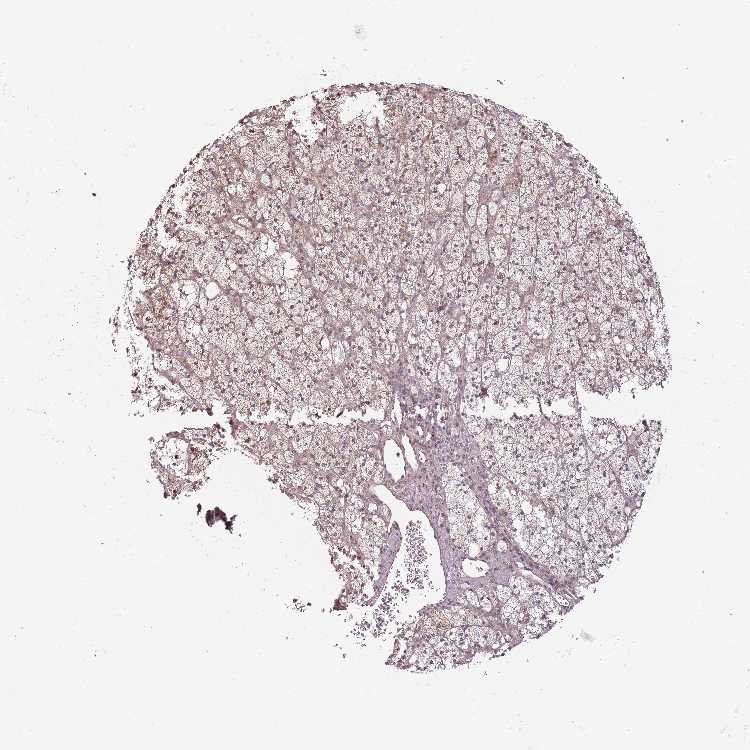

ADRENAL GLAND - Antibody stainingi

Antibody staining in the annotated cell types in the current human tissue is reported as not detected, low, medium, or high, based on conventional immunohistochemistry profiling in selected tissues. This score is based on the combination of the staining intensity and fraction of stained cells.

Each image is clickable and will lead to virtual microscopy that enables deeper exploration of all samples and also displays staining intensity scores, fraction scores and subcellular localization as well as patient and tissue information for each sample.

Antibody HPA040072

Glandular cells Low